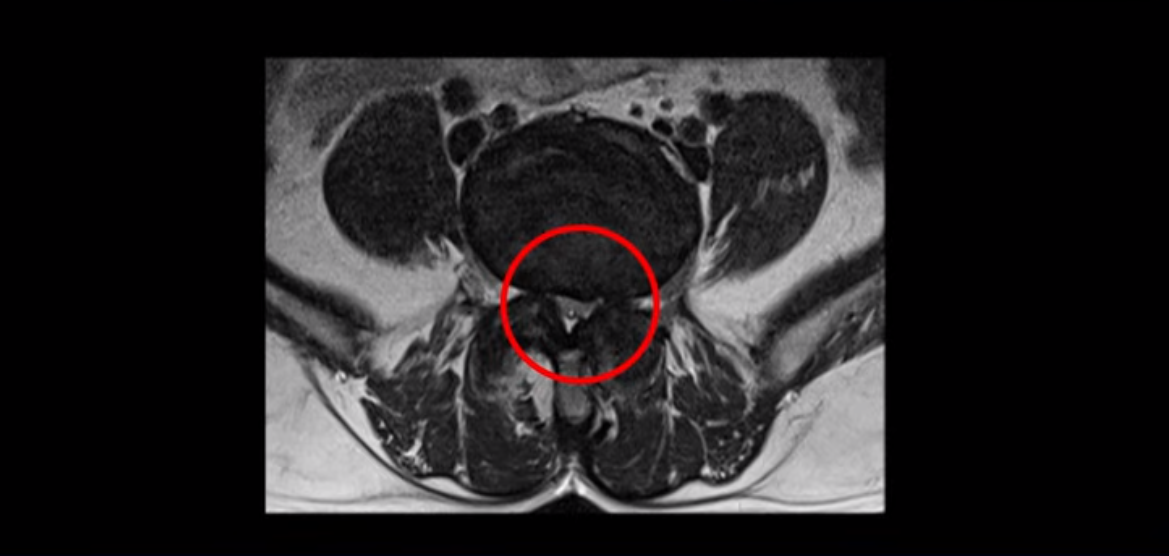

단면으로 보면 왼쪽 후궁을 제거한 흔적이 보입니다.

5번 1번도 왼쪽 후궁을 열고 수술 받았습니다.

하지만 중심성 협착은 여전히 심한 상태입니다.

이분은 오른쪽, 왼쪽 다리에 모두 방사통이 심하고 왼쪽 다리에 마비 증상, 즉 풋드랍(족하수) 증상이 있습니다. 왼쪽 신경 가지가 빠져나가는 추간공을 보면 두 마디가 좁아져 있습니다.

이런 신경 구멍이 좁아져 있는 걸 협착이라고 합니다.

이미 앞선 두 번의 수술로 뼈와 인대 등을 일부 제거해서 안정성이 떨어진 상태에서 추가로 수술하려니까 척추가 너무 불안정해져 무너질 게 걱정되니까 이번에는 나사 박는 유합술을 권유 받은 겁니다. 이런 환자분들의 방사통과 마비 증상이 어떻게 수술 없이 좋아질 수 있을까요? 치료는 어떻게 하는 걸까요?